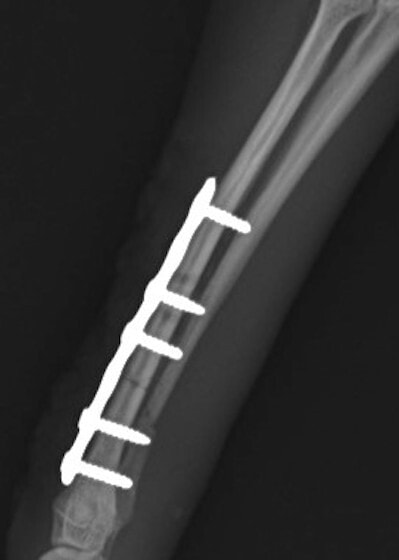

症例3:キルシュナーワイヤーのピンニングによる整復

ペルシャ猫 11ヶ月齢 雄

他院にて左大腿骨遠位の成長板骨折(salter-harrisⅠ型)が認められており、治療相談を目的として来院。当院にて、キルシュナーワイヤーを用いたピンニングにより骨折部位の整復を行いました。術後の経過は良好で、現在も経過観察中です。

術前レントゲン

術後レントゲン

Arthrex社のターゲティングデバイスを用いてピンニングの位置を調整することで、確実な固定を行っています。当院ではこの手術器具以外にも、人の手術にも使用される様々な器具を導入し、手術精度を高め、また医療メーカーと新しい器具の開発、試作にも取り組んでおります。